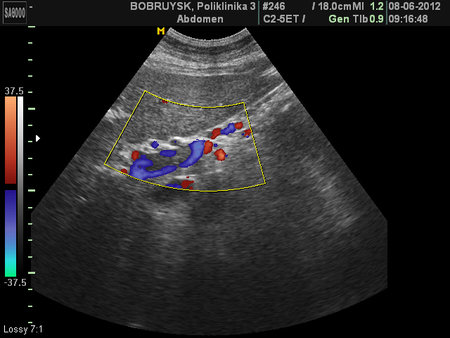

- Тромбоз правой и левой ветвей воротной вены

- ЦДК, промб в левой ветви ВВ.

- Порто-портальные коллатерали